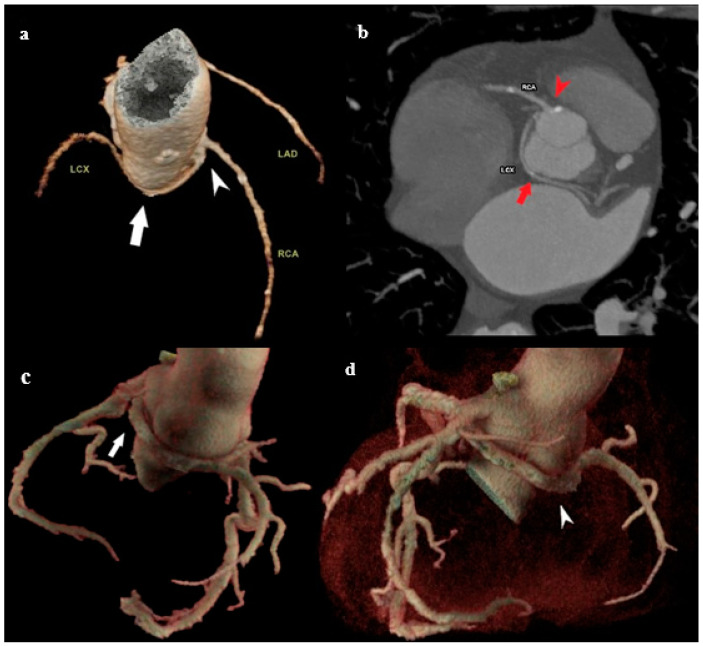

冠状动脉可在数量、起始点或路线上变化。这些变异属于冠状动脉解剖变异/异常的范畴,代表冠状动脉血管系统的先天性异常。通常,它们是良性的,无症状的,并且在为其他适应症进行冠状动脉造影时无意中被发现。然而,在某些情况下,异常的特征或其与周围结构的相互作用可能导致血流动力学紊乱。这些紊乱会导致血流紊乱,进而增加动脉粥样硬化和心肌缺血的可能性。如果有症状,潜在的表现包括胸痛、心律失常、晕厥、心肌梗死和心源性猝死。鉴于在某些情况下可能危及生命的并发症,早期和准确的诊断冠状动脉异常是至关重要的。用于评估冠状血管的最常用的诊断程序是冠状血管造影和多探测器行计算机断层扫描(MDCT)冠状血管造影。多层螺旋ct血管造影是一种无创、可靠、安全、灵敏的冠状动脉详细解剖可视化方法。它提供高分辨率成像,能够精确评估先天性冠状动脉变异,有助于临床决策和长期患者管理。我们进行了一项叙述性的回顾,分析和整合了大量关于冠状动脉变异和异常的文献。我们的目的是提供一个全面的,尽管不是详尽的,关于其定义、分类和MDCT血管造影检测的基本概念和发现的概述。通过整合MDCT成像的现有知识,我们寻求更好地理解冠状动脉变异的临床意义及其在心血管健康中的作用。

Coronary arteries may vary in quantity, point of origin, or course. These variations fall under the category of anatomical variants/anomalies of the coronary arteries, representing congenital abnormalities of the coronary vascular system. Generally, they are benign, asymptomatic, and identified inadvertently during coronary angiography conducted for alternative indications. However, in some cases, the anomaly's characteristics or its interaction with surrounding structures may cause hemodynamic disturbances. These disturbances can lead to turbulent blood flow, which in turn poses an increased likelihood for the development of atherosclerosis and myocardial ischemia. If symptomatic, potential manifestations include chest pain, arrhythmias, syncope, myocardial infarction, and sudden cardiac death. Given the potential for life-threatening complications in certain cases, the early and accurate diagnosis of coronary artery anomalies is of paramount importance. The most common diagnostic procedures used for the evaluation of coronary vessels are coronary angiography and multi-detector row computed tomography (MDCT) coronary angiography. MDCT angiography is a non-invasive, dependable, safe, and sensitive method for the detailed visualization of coronary anatomy. It offers high-resolution imaging that enables precise assessment of congenital coronary variations, aiding in both clinical decision-making and long-term patient management. We conducted a narrative review to analyze and integrate the body of literature on coronary artery varieties and anomalies. Our objective was to provide a comprehensive, albeit non-exhaustive, overview of essential concepts and findings related to their definition, classification, and detection with MDCT angiography. By integrating current knowledge in MDCT imaging, we seek to contribute to a better understanding of the clinical implications of coronary artery variations and their role in cardiovascular health.